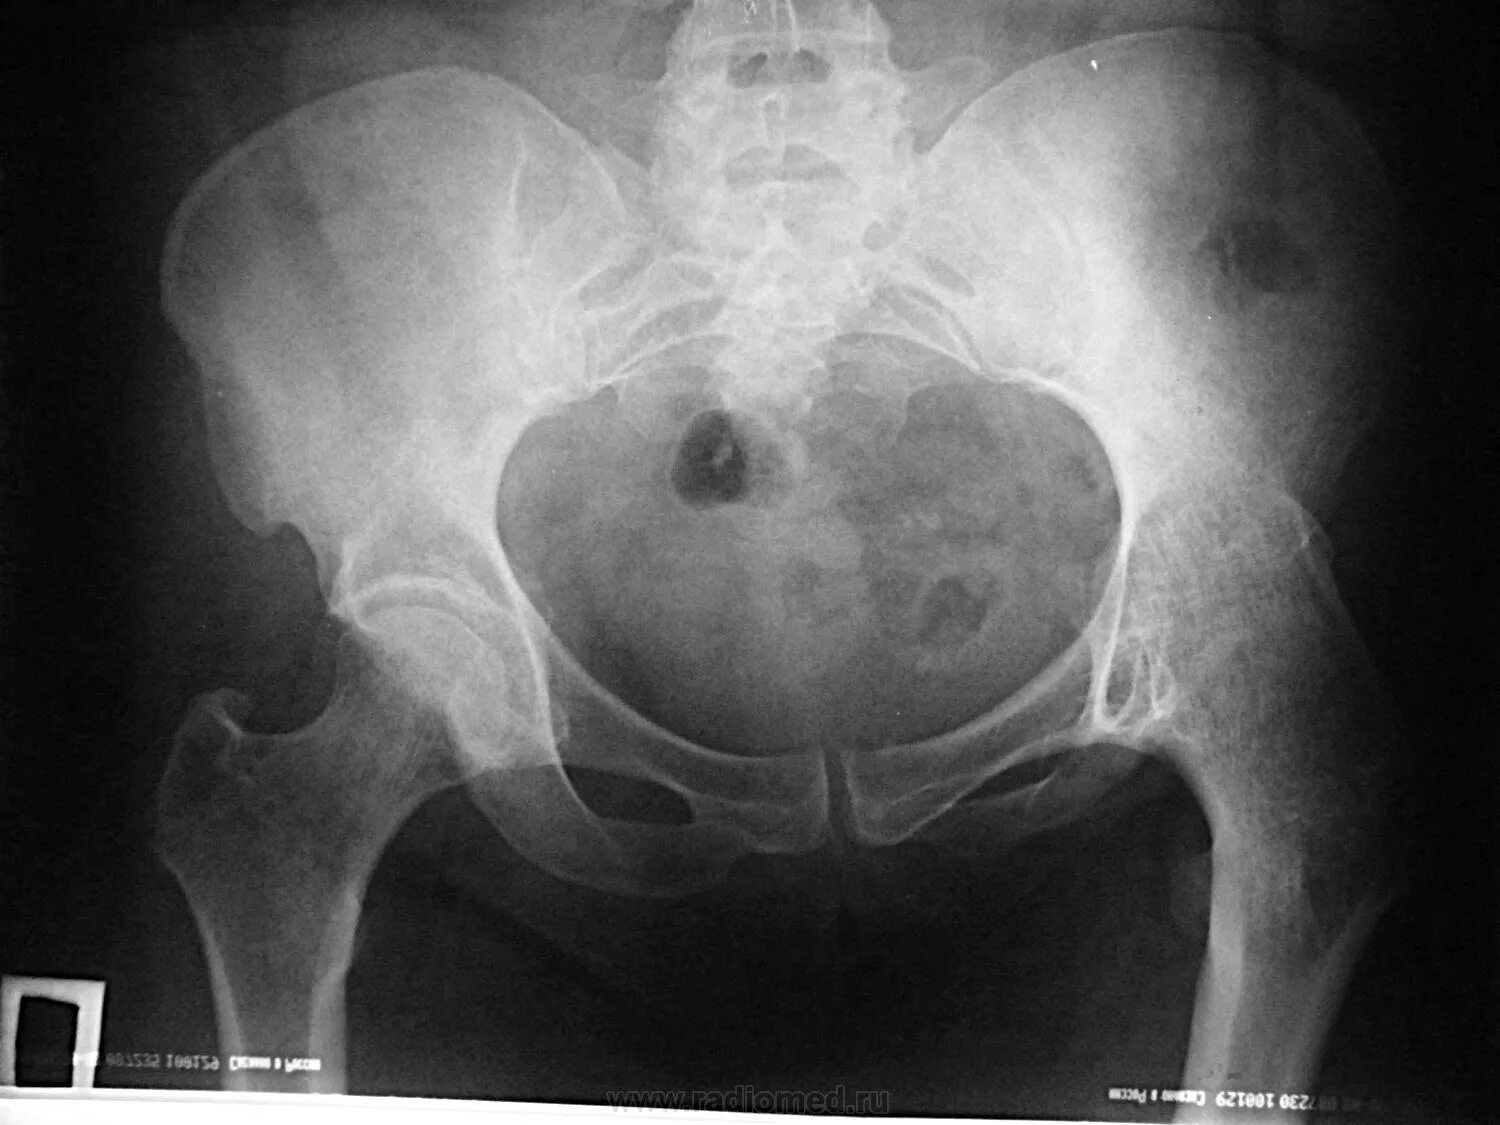

Анкилоз тазобедренного сустава